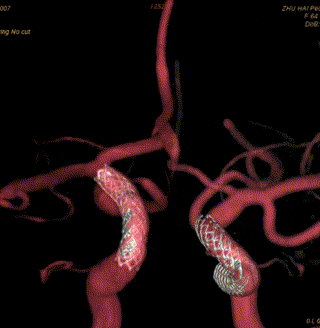

脑血管造影提示右侧颈内动脉颅内段多发动脉瘤(反主动脉弓)

脑血管造影提示右侧颈内动脉颅内段多发动脉瘤

4mm×30mm Streamline

术后4月余随访:多发动脉瘤均未见显影,远端残余轻度狭窄

术前术后对比